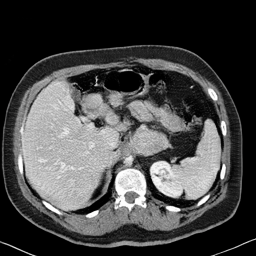

In many clinical settings, the use of both Computed Tomography (CT) and Magnetic Resonance (MRI) is necessary to pursue a thorough understanding of the patient's anatomy and to plan a suitable therapeutical strategy; this is often the case in MRI-based radiotherapy, where CT is always necessary to prepare the dose delivery, as it provides the essential information about the radiation absorption properties of the tissues. Sometimes, MRI is preferred to contour the target volumes. However, this approach is often not the most efficient, as it is more expensive, time-consuming and, most importantly, stressful for the patients. To overcome this issue, in this work, we analyse the capabilities of different configurations of Deep Learning models to generate synthetic CT scans from MRI, leveraging the power of Generative Adversarial Networks (GANs) and, in particular, the CycleGAN architecture, capable of working in an unsupervised manner and without paired images, which were not available. Several CycleGAN models were trained unsupervised to generate CT scans from different MRI modalities with and without contrast agents. To overcome the problem of not having a ground truth, distribution-based metrics were used to assess the model's performance quantitatively, together with a qualitative evaluation where physicians were asked to differentiate between real and synthetic images to understand how realistic the generated images were. The results show how, depending on the input modalities, the models can have very different performances; however, models with the best quantitative results, according to the distribution-based metrics used, can generate very difficult images to distinguish from the real ones, even for physicians, demonstrating the approach's potential.